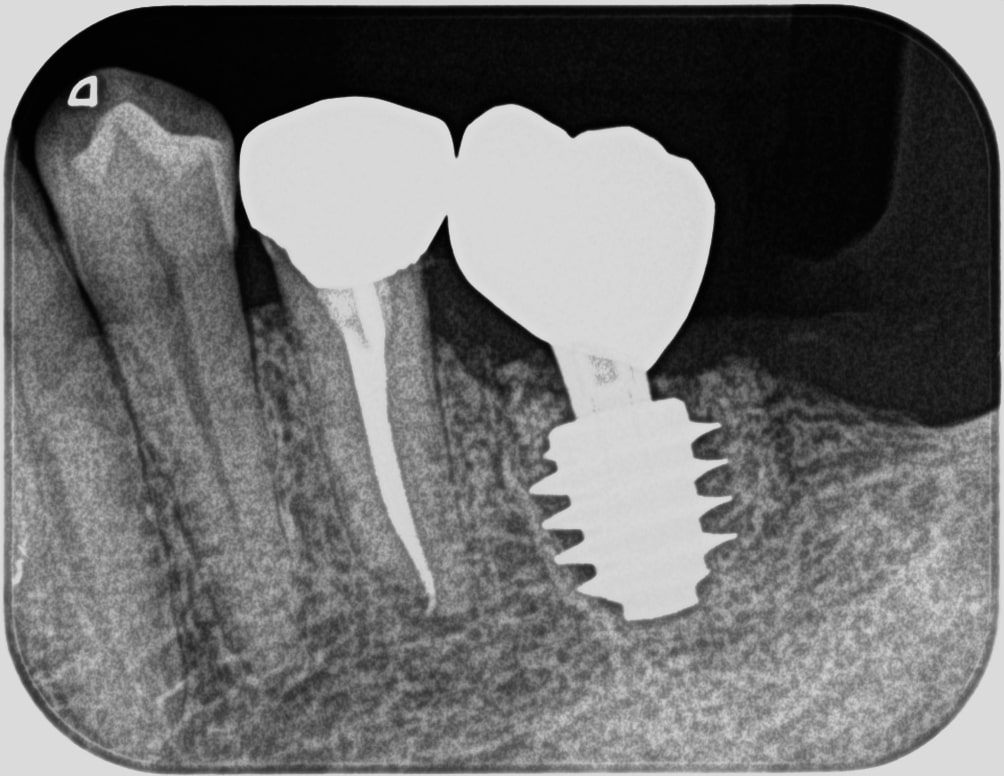

症例260代 女性 主訴 グラグラして噛めない

治療前

治療後

治療前

治療後

グラついていて奥歯でしっかり噛めないと訴え来院。

力学的に強いインプラントを選択。右下6番に埋入。

オペ後、骨との密着値も良く、約2ヶ月後には、ジルコニアを装着し終了。

リスクとしては外科的侵襲がある。デメリットは、保険外診療の為、経済的負担がある。

費用 58万(税込)(オペ・仮歯・最終補綴物まで含む)